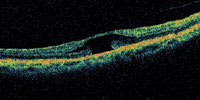

| Figure 4. A patient with an irregular shape to the fovea. This may represent a lamellar macular hole or a self-healed full-thickness macular hole. |

A central clinical challenge has been accurately diagnosing early macular holes which may be mimicked by many other conditions.34,35 No imaging modality has enhanced our diagnostic capability more than the OCT; superior imaging capabilities have improved diagnostic accuracy, clinical monitoring, and postoperative assessment.36-38 The OCT unequivocally demonstrates early stages of full-thickness macular holes (Figure 1), and allows distinction of pseudohole and pre-macular hole conditions in almost all instances. Fluid accumulation in early, presumed pre-macular hole stages have been corroborated by OCT observations (Figure 2). Serial images have been reported showing the progression from apparent impending macular holes to full thickness macular holes.39-42 It has depicted many other configurations that might be in the spectrum of lamellar or pre-macular hole conditions (Figure 3 and 4).